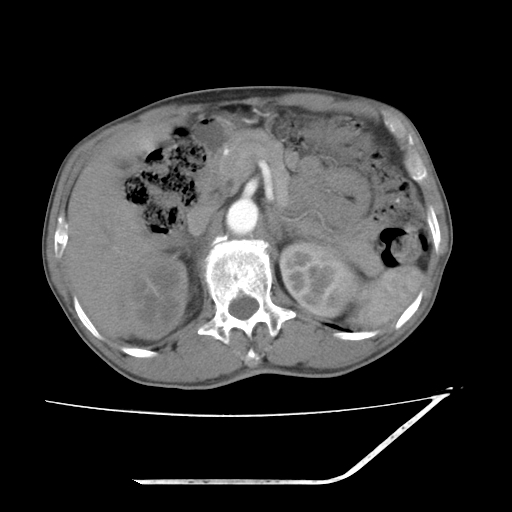

考虑右肾盂癌,肾动脉受侵,右肾功能减退,右肾盂输尿管积水,管壁增厚,考虑种植转移,应该把下面扫完的

考虑右侧肾盂癌。右侧输尿管扩张未扫描完。

右肾盂癌,肾动脉受侵,右肾盂输尿管积水,管壁增厚,考虑种植转移

右肾盂移行细胞癌并右输尿管中段转移.肾积水.

1.右侧肾盂癌伴肾盂积水。

3.右侧上段输尿管扩张,原因:(1)积水所致;(2)种植。